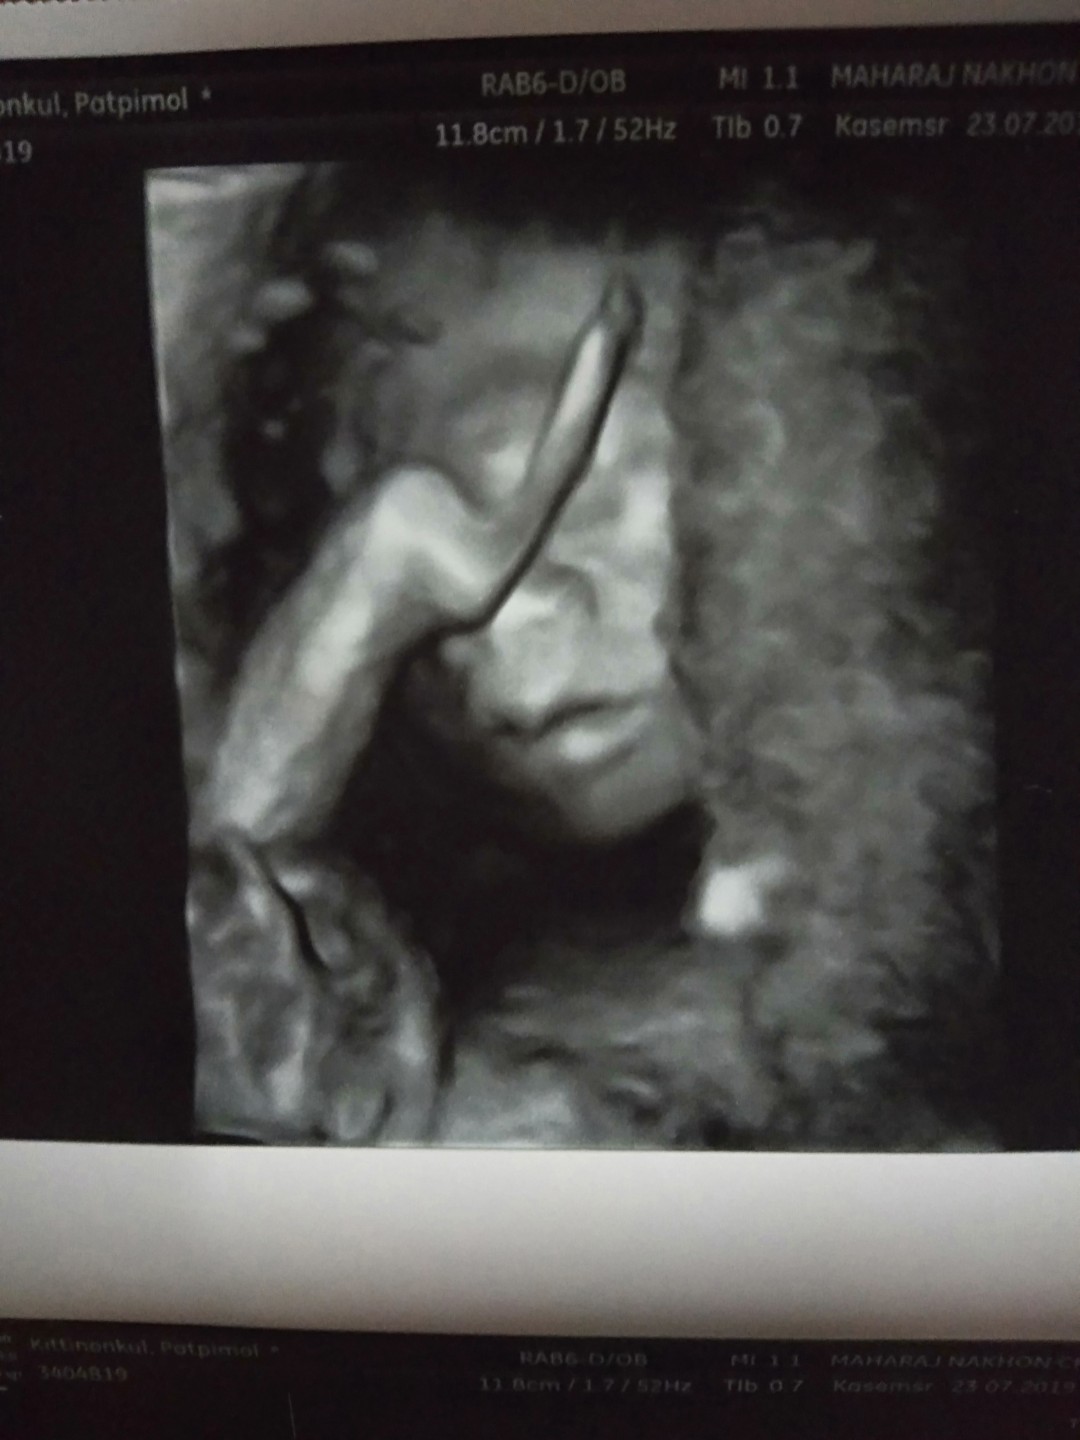

แม่บ้านนี้อยากได้ลูกสาวค่ะ #กำหนดคลอด 12 ธันวาคม #รูปซาวด์ตอน 12W